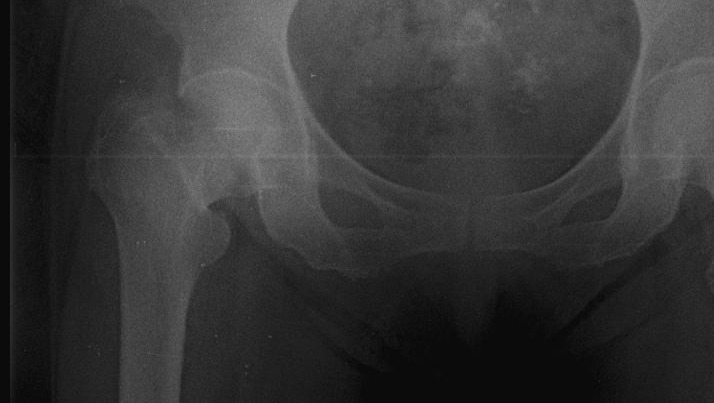

The only option to heal her hip is an immediate surgery wherein a prosthetic hip would replace her broken one allowing her to walk in less than a week. Safe, reliable medical centers in Venezuela are few and far between so finding one that is willing to do this surgery is extremely expensive and not covered by any sort of insurance.

I'm attaching pictures of the fracture as well as the prosthetic surgery that would completely restore her hip.